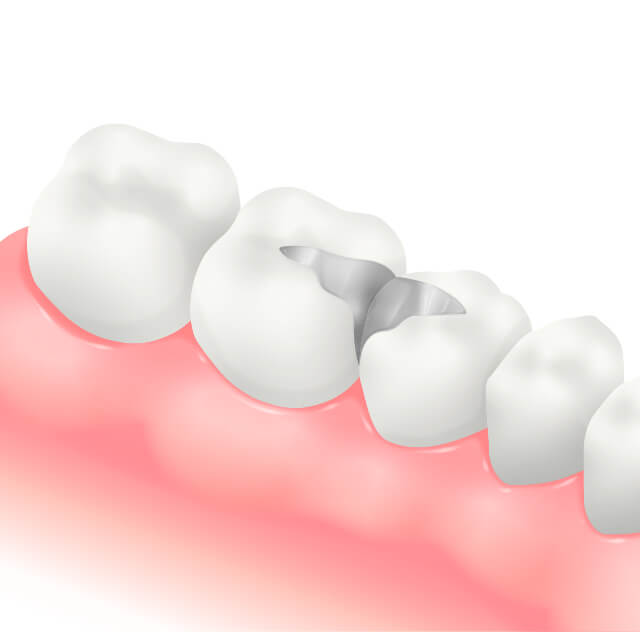

メタルインレー(詰め物)

奥歯の中等度以上のむし歯に対して行う詰め物で、型をとり技工士に作製してもらいはめ込むため治療回数がかかる。

また、金属は年数の経過とともに変形するため隙間ができる可能性が高く、その隙間から細菌が侵入し、むし歯が再発してしまう可能性がある。審美性も優れない。

メタルクラウン(奥歯被せ物)

奥歯に対しての被せ物。メタルインレーでは対応できない大きなむし歯や根管治療終了後のケースに使用される。

金属は年数の経過とともに変形するため隙間ができむし歯が再発してしまう可能性がある。

また、金属なので審美的に優れない。